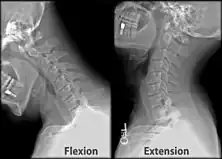

Cervical degenerative changes arise from conditions such as spondylosis, stenosis of intervertebral discs, and the formation of osteophytes. The changes are seen on radiographs, which are used in a grading system from 0–4 ranging from no changes (0) to early with minimal development of osteophytes (1) to mild with definite osteophytes (2) to moderate with additional disc space stenosis or narrowing (3) to the stage of many large osteophytes, severe narrowing of the disc space, and more severe vertebral end plate sclerosis (4).[5][6][7]

X-ray of cervical spine in flexion and extension